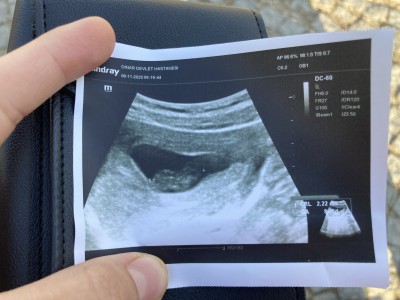

Kızlar bebeğimin kalbinin sesini duyamadık doktor 6 haftalıkken gittik 3 hafta önce bebek ufak tu şimdi büyümüş 1 hafta geriden gelmiş dedi ne yapayım böyle olup da sonra duyan oldu mu image

Daha erken kalp atışı için. 8 haftalık olduğunda tekrar gidin. O zaman inşallah duyarsnz

Biraz daha beklyebilirsiniz içinizin rahat olması açısından bide hcg değerinizi 2 fun arayla kontrol ettirin değer dusuyo mu artiyomu diye ben başla türlü ikna olamamıştım